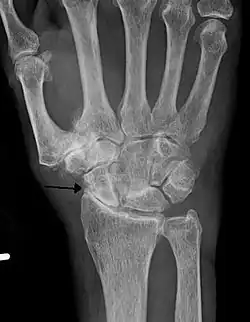

Lateral X-ray scan of ankle with secondary osteoarthritis

Lateral

Frontal X-ray scan of ankle with secondary osteoarthritis

Frontal

Secondary osteoarthritis of the ankle (due to an old bone fracture) in an 82-year-old woman

Diagnosis is made with reasonable certainty based on history and clinical examination.[52][53] X-rays may confirm the diagnosis. The typical changes seen on X-ray include: joint space narrowing, subchondral sclerosis (increased bone formation around the joint), subchondral cyst formation, and osteophytes.[54] Plain films may not correlate with the findings on physical examination or with the degree of pain.[55]